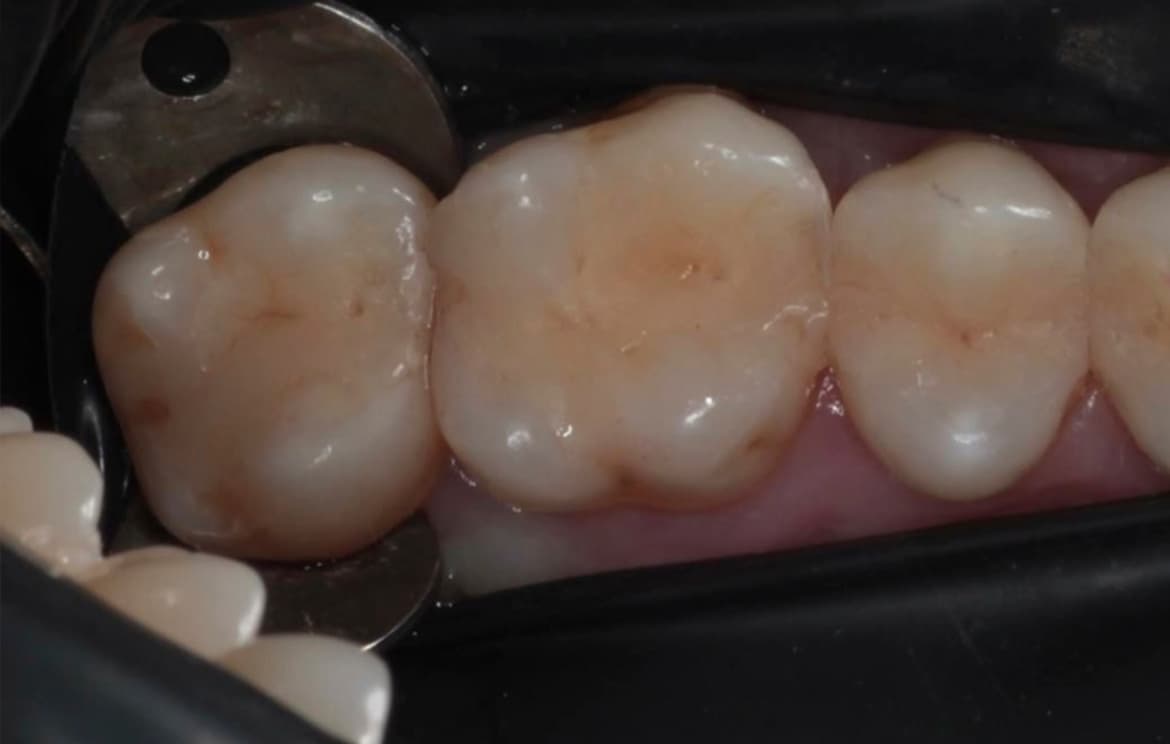

Наши работы